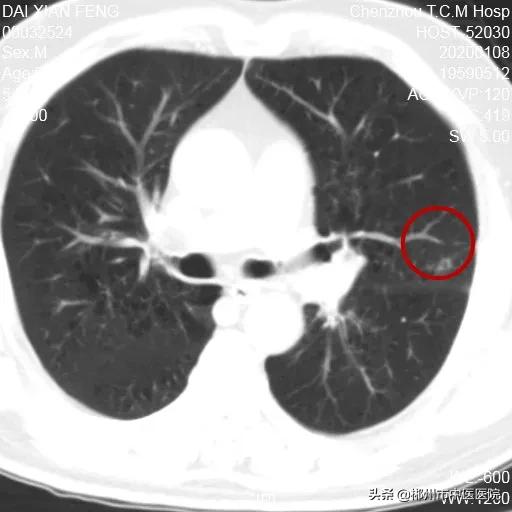

2020年1月8日治疗两个月后第一次复查

病灶基本消退呈环形改变

第一次复查残留区域7X6mm